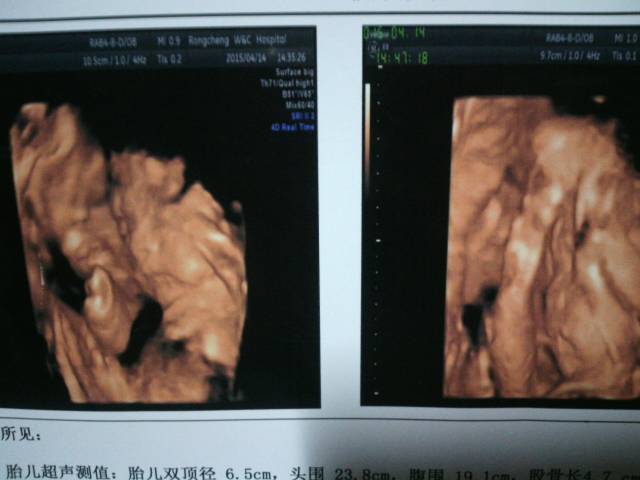

今天又做了一次四维,宝宝嘴唇也挺好的,发育都挺好,放心了,嘻嘻… 今天又做了一次四维,宝宝嘴唇也挺好的,发育都挺好,放心了,嘻嘻。。。。 点击展开 总有一颗想玩的心 2015-04-14 21:02 为您推荐: 其他回答 祝宝妈好孕! 蓝色的秋叶 2015-04-14 22:09 恭喜你呀! 保定亿家馨家政月嫂育婴师 2015-04-14 21:48 健康就好! 不得╮我就跑 2015-04-14 21:24 很可爱的宝宝 遗忘.ˊing 2015-04-14 21:23 您好,宝宝健康,妈妈也会很开心,祝你生个健康的小宝宝,宝宝以后健康成长 ľǿ 2015-04-14 21:19 加载更多 相关问题 这两次检查医生说宝宝的嘴唇不好,可做四维照片时,医生当时说挺好的!到底怎么办? 怀孕36周了,请问我现在还需要做什么检查,以前只做了,2次四维彩超,医生说什么也没事,都挺好的 前几 今天去做了四维,结果出来除了宝宝的嘴唇可以看到大概的形状之外,其他的什么都看不了!请各位帮忙看看